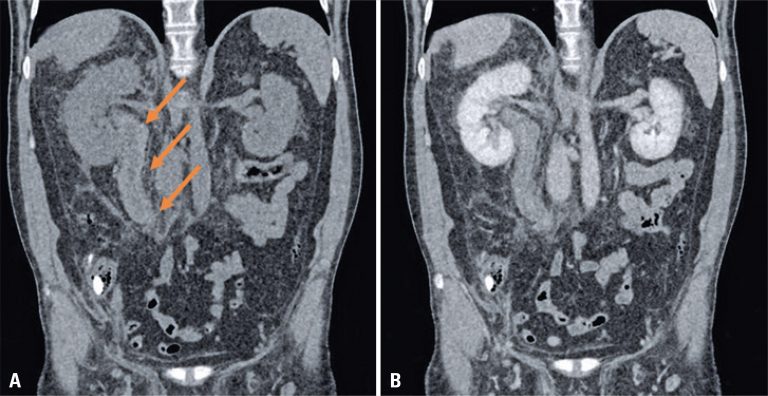

A 49-year-old man came to our emergency department with a 2-day history of fever, cough, anosmia, ageusia and odynophagia. His past medical history included hypertension. At the time of this presentation, chest computed tomography revealed peripheral and bilateral ground-glass opacities, with some visible intralobular lines – typical findings of pneumonia caused by the severe acute respiratory syndrome coronavirus 2 (SARS-CoV-2). In addition, some findings revealed the target sign (). The patient’s supportive treatment was continued, and reverse-transcriptase polymerase chain reaction […]